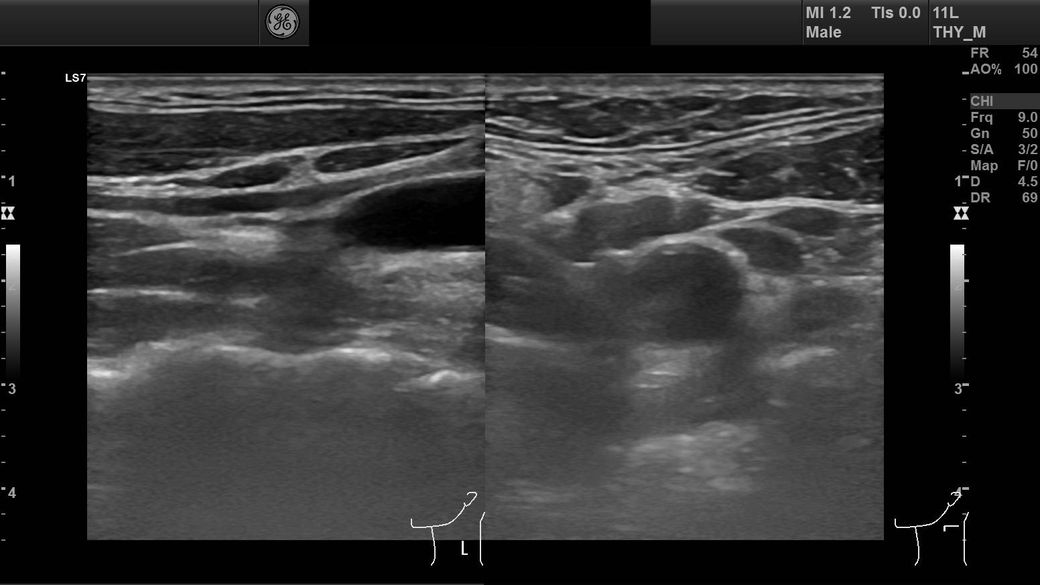

경부초음파사진 결과 사진 질문드립니다

임파선이 부어서 초음파를 찍었는데

어떤 사진인지는 모르겠는데 혈관이 왼쪽에 비해 오른쪽이 좁다고 하셨는데 이게 큰 문제가 있는건가요?

• 3번 째 사진

혈관이 좁다고 했다면 경동맥을 말하는 것 같습니다

경동맥의 경우 2D로 관찰을 했을 때 내강이 절반이 되더라고 전체면적으로 봤을 떄는 많이 좁아진 것이 아니니

크게 걱정하지 않으셔도 됩니다

판독기록에 어느 정도 좋아졌는지 확인을 해보세요